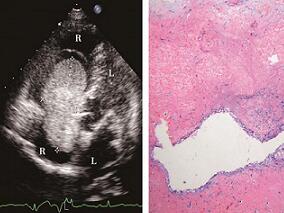

1小时条评论病例摘要 女性,52岁。主因 活动后胸闷、憋气伴乏力1个月余入院。 现病史 患者于1个月前因 活动后胸闷憋气、乏力在国外就诊,超声心动图提示右心房占位性病变 (黏液瘤可能)、三尖瓣反流。回国后外院超声心动图回报为:右心房内可见中等回声团块以短细蒂附着于房间隔...